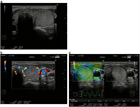

1. 甲状腺結節性病変に対して、超音波上の特徴的な所見を分析することで、良性結節をより的確に診断し、不必要な穿刺吸引細胞診を減らすことができる(推奨度2)

1. 超音波で悪性を疑う所見としては、縦横比>1(感度40.0%、特異度91.4%)、境界部棘状(感度48.3%、特異度91.8%)、著明な低エコー(感度41.4%、特異度92.2%)、微細石灰化(感度44.2%、特異度90.8%)、粗大石灰化(感度9.7%、特異度96.1%)であった(推奨度2)